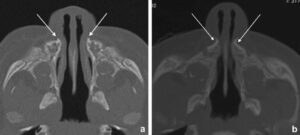

بعد از آن، تشخیص تنگی فک بالا با عکس رادیوگرافی برای اطمینان از نوع تشخیص شکل میگیرد. رادیوگرافی پانورامیک (OPG) عرض فک را نشان میدهد و CBCT مدل سه بعدی دقیقی از استخوانها میسازد. بعد از آن پزشک متخصص تصمیم میگیرد عمل فک را انجام دهد یا روش دیگری را در پیش بگیرد.